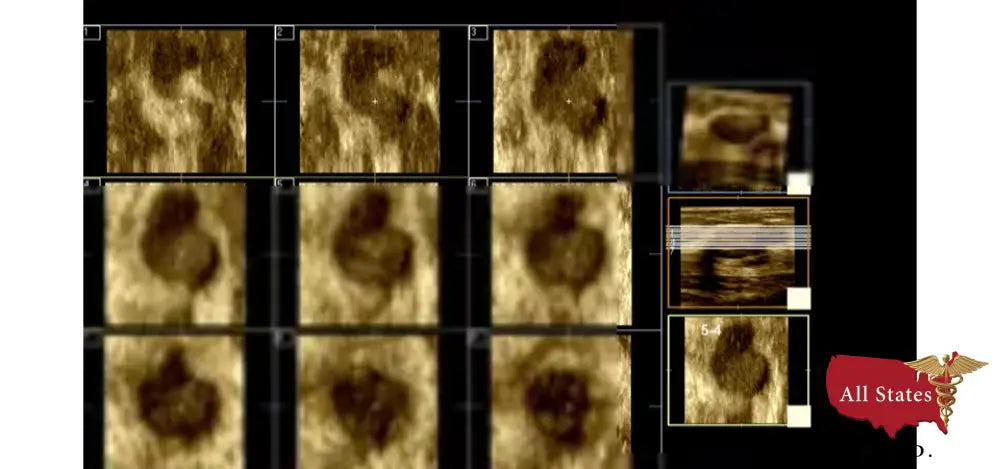

Expand diagnostic information

The CX50 offers assessment and analysis capabilities with QLAB’s Q‐Apps: GI 3D quantification (GI 3DQ, Region of interest (ROI, Intima media thickness evaluation (IMT, Cardiac motion quantification with speckle tracking technology (CMQ, Strain quantification (SQ, and MicroVascular imaging (MVI